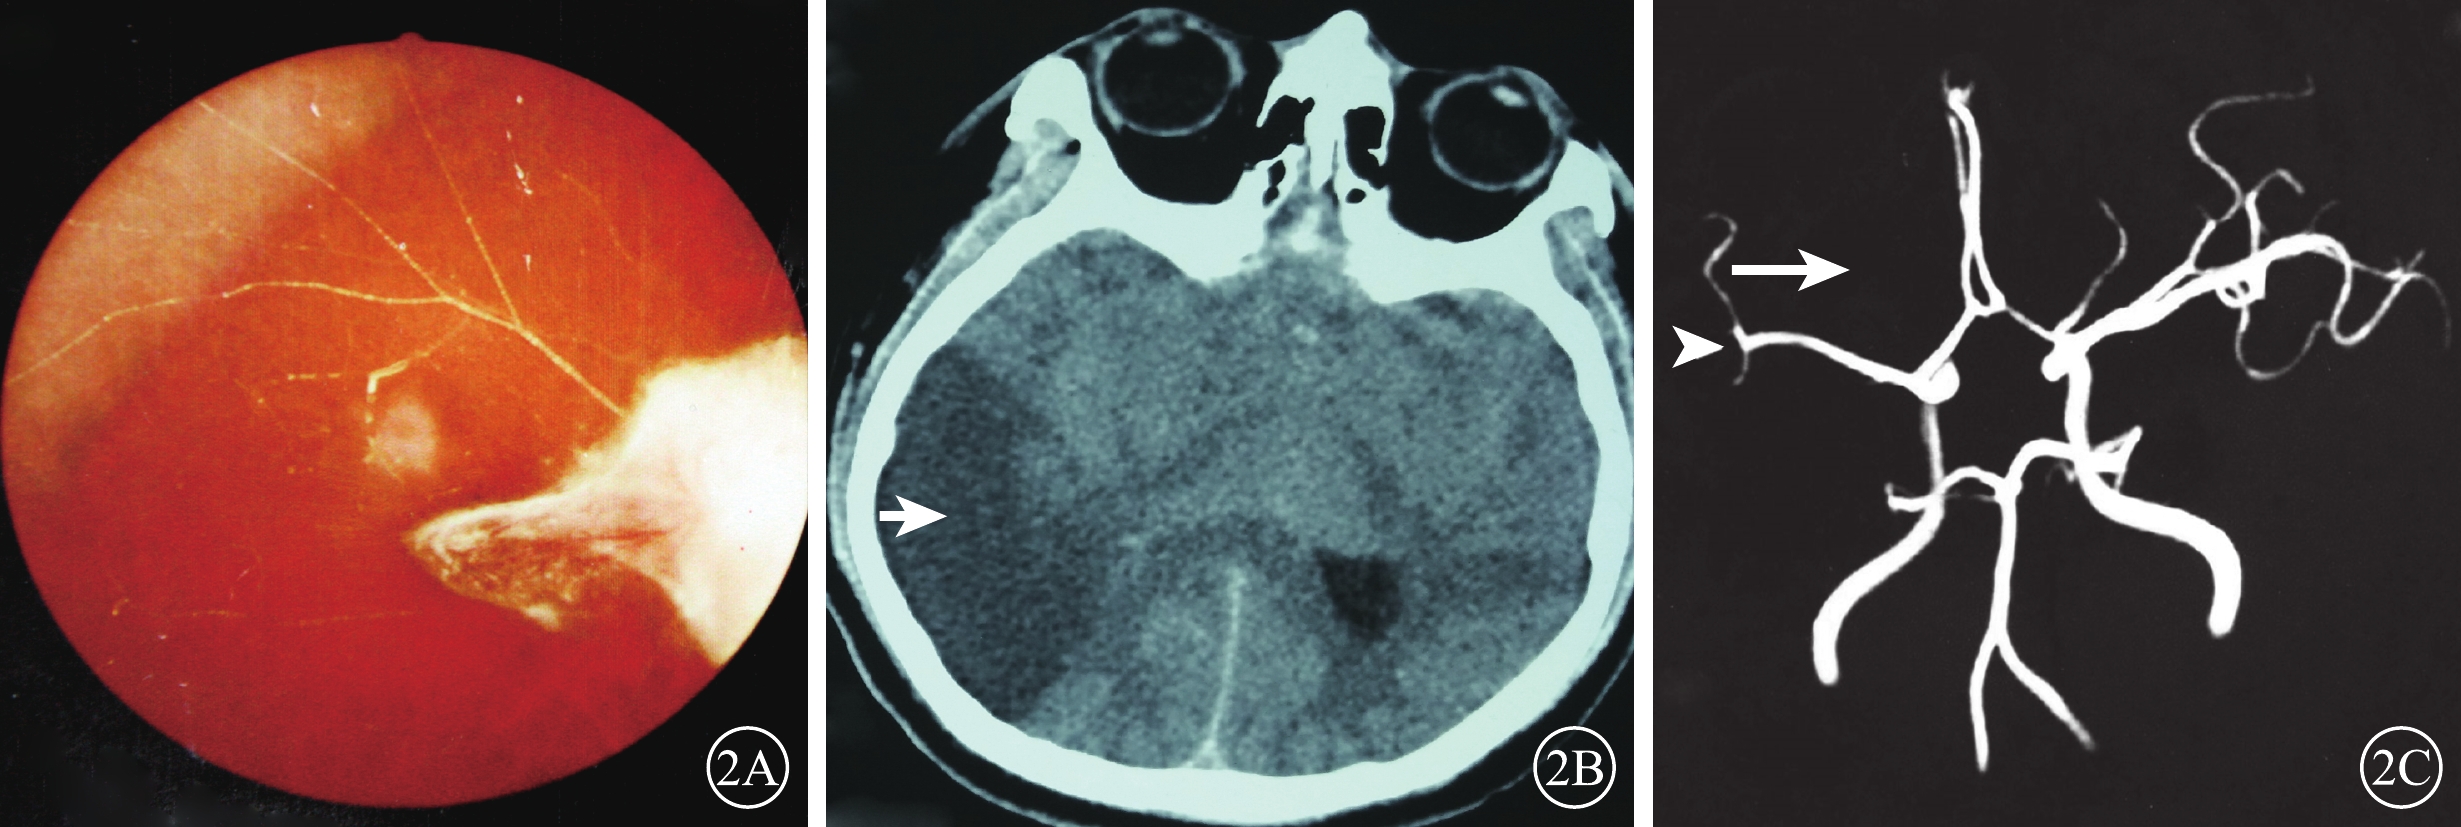

患眼視力無光感~0.6。20只眼中,單純OAO 3只眼(15%);OAO合并CAO 4只眼(20%)、MAO 1只眼(5%);單純RAO 7只眼(35%),其中CRAO(圖1)、HRAO、BRAO分別為4、1、2只眼;CRAO伴PCAO 1只眼(5%);PCAO伴NAION 1只眼(5%);CRAO合并DNAO 2只眼(10%);CRAO、PCAO合并右大腦中動脈阻塞1只眼(5%)(表2)。20例中,眼球運動障礙和眼瞼皮膚發紺4例(20%);合并面部疼痛、鼻部皮膚缺血壞死2例(10%)。顱腦CT檢查示右側大腦中動脈供血區域低密度缺血灶1例(20%)。MRA檢查發現顱內新發缺血灶6例(30%)。6例患者中,玻尿酸注射者5例,均為無癥狀的小血管阻塞。自體脂肪注射者1例,男,27歲。右眼視力無光感,眼球運動障礙;左側肢體偏癱。眼底可見后極部灰白色水腫,黃斑中心凹反光消失(圖2A);顱腦CT檢查,右側顳葉低密度梗死灶(圖2B);MRA檢查,右側眼動脈未顯影,大腦中動脈M2段閉塞(圖2C)。

圖2

序號7患者彩色眼底、CT、MRA像。2A示右眼彩色眼底像,顳上血管白線狀,其余血管消失;視盤結構不清,其顳側灰白色極化灶。2B示CT像,右側顳葉低密度梗死灶(白箭);2C示MRA像,右側眼動脈未顯影(白箭),大腦中動脈M2段閉塞(白箭頭)

圖2

序號7患者彩色眼底、CT、MRA像。2A示右眼彩色眼底像,顳上血管白線狀,其余血管消失;視盤結構不清,其顳側灰白色極化灶。2B示CT像,右側顳葉低密度梗死灶(白箭);2C示MRA像,右側眼動脈未顯影(白箭),大腦中動脈M2段閉塞(白箭頭)

患眼視力無光感~0.6。20只眼中,單純OAO 3只眼(15%);OAO合并CAO 4只眼(20%)、MAO 1只眼(5%);單純RAO 7只眼(35%),其中CRAO(圖1)、HRAO、BRAO分別為4、1、2只眼;CRAO伴PCAO 1只眼(5%);PCAO伴NAION 1只眼(5%);CRAO合并DNAO 2只眼(10%);CRAO、PCAO合并右大腦中動脈阻塞1只眼(5%)(表2)。20例中,眼球運動障礙和眼瞼皮膚發紺4例(20%);合并面部疼痛、鼻部皮膚缺血壞死2例(10%)。顱腦CT檢查示右側大腦中動脈供血區域低密度缺血灶1例(20%)。MRA檢查發現顱內新發缺血灶6例(30%)。6例患者中,玻尿酸注射者5例,均為無癥狀的小血管阻塞。自體脂肪注射者1例,男,27歲。右眼視力無光感,眼球運動障礙;左側肢體偏癱。眼底可見后極部灰白色水腫,黃斑中心凹反光消失(圖2A);顱腦CT檢查,右側顳葉低密度梗死灶(圖2B);MRA檢查,右側眼動脈未顯影,大腦中動脈M2段閉塞(圖2C)。

圖2

序號7患者彩色眼底、CT、MRA像。2A示右眼彩色眼底像,顳上血管白線狀,其余血管消失;視盤結構不清,其顳側灰白色極化灶。2B示CT像,右側顳葉低密度梗死灶(白箭);2C示MRA像,右側眼動脈未顯影(白箭),大腦中動脈M2段閉塞(白箭頭)

圖2

序號7患者彩色眼底、CT、MRA像。2A示右眼彩色眼底像,顳上血管白線狀,其余血管消失;視盤結構不清,其顳側灰白色極化灶。2B示CT像,右側顳葉低密度梗死灶(白箭);2C示MRA像,右側眼動脈未顯影(白箭),大腦中動脈M2段閉塞(白箭頭)